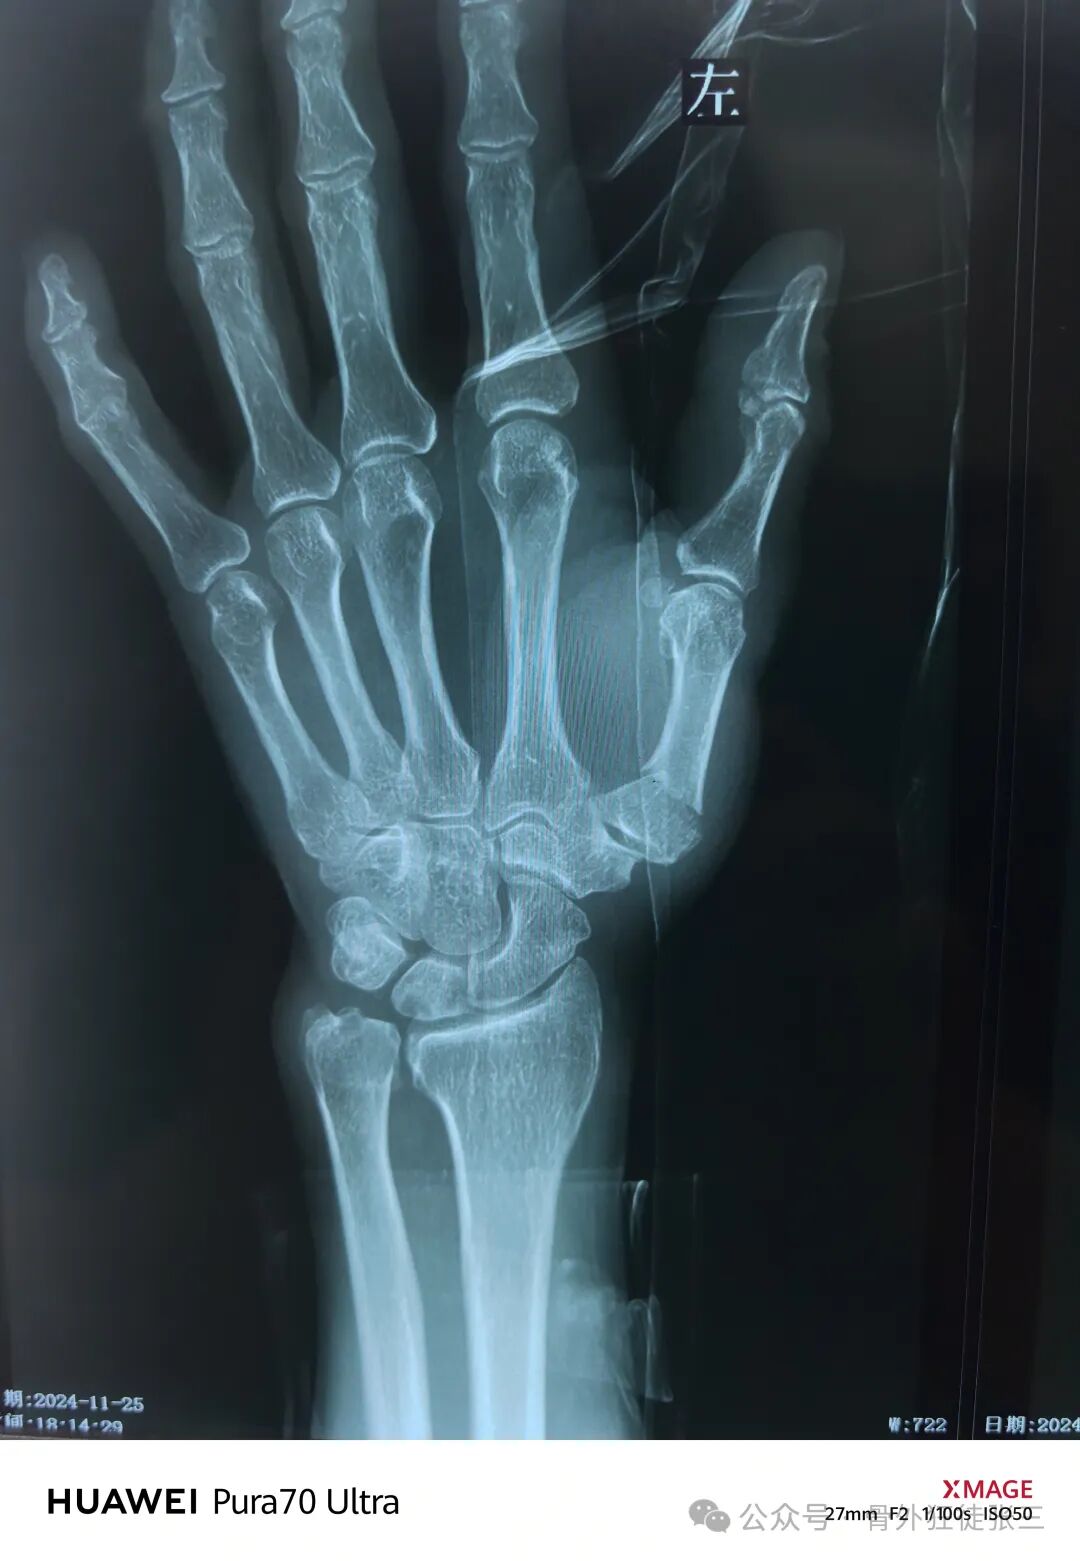

二、Rolando骨折

病例3:

原图用了近端小T板/一枚横向克氏针+远端两枚横向克氏针,我们一般采用闭合复位,近端1-2枚克氏针,远端2枚,撑开虎口,保持外展,维持拇指对掌位。